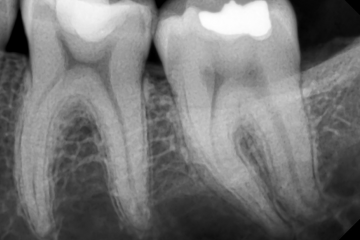

- Slikanje zobnih kronali bitewing